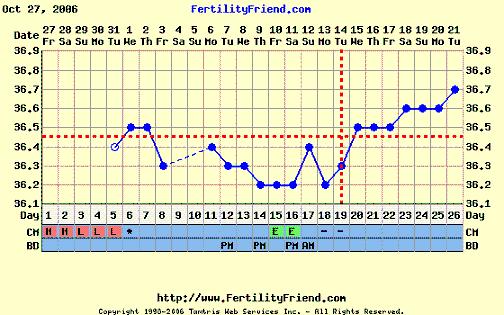

A görbédhez:ha holnap vagy holnap után visszamegy a hőd, akkor nagyon baba gyanús a görbéd

Szirom, szerintem is még korai volt a teszt. Most 13 dpon vagy, varj egy párj napot, a görbéd nagyon szép, ha nem megy holnap lejebb a hőd két nap és tesztelj.

Robcsi, a Te görbéd aztán tényleg kacifántos, de akár mi is lehet, a ferty-n is vannak különleges görbék amiből végül baba lett.